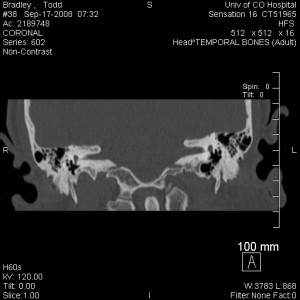

Long story short: He confirmed that I have superior canal dehiscence on the right side, just as we suspected from the MRI results last week and from my history. I may have it on the left side, too, but the right side is the one that’s bothering me.

Below is the image that (according to the doctors) is the smoking gun. If you knew what to look for you could see that the top part of the superior canal has dehisced, or opened up, into the brain cavity.